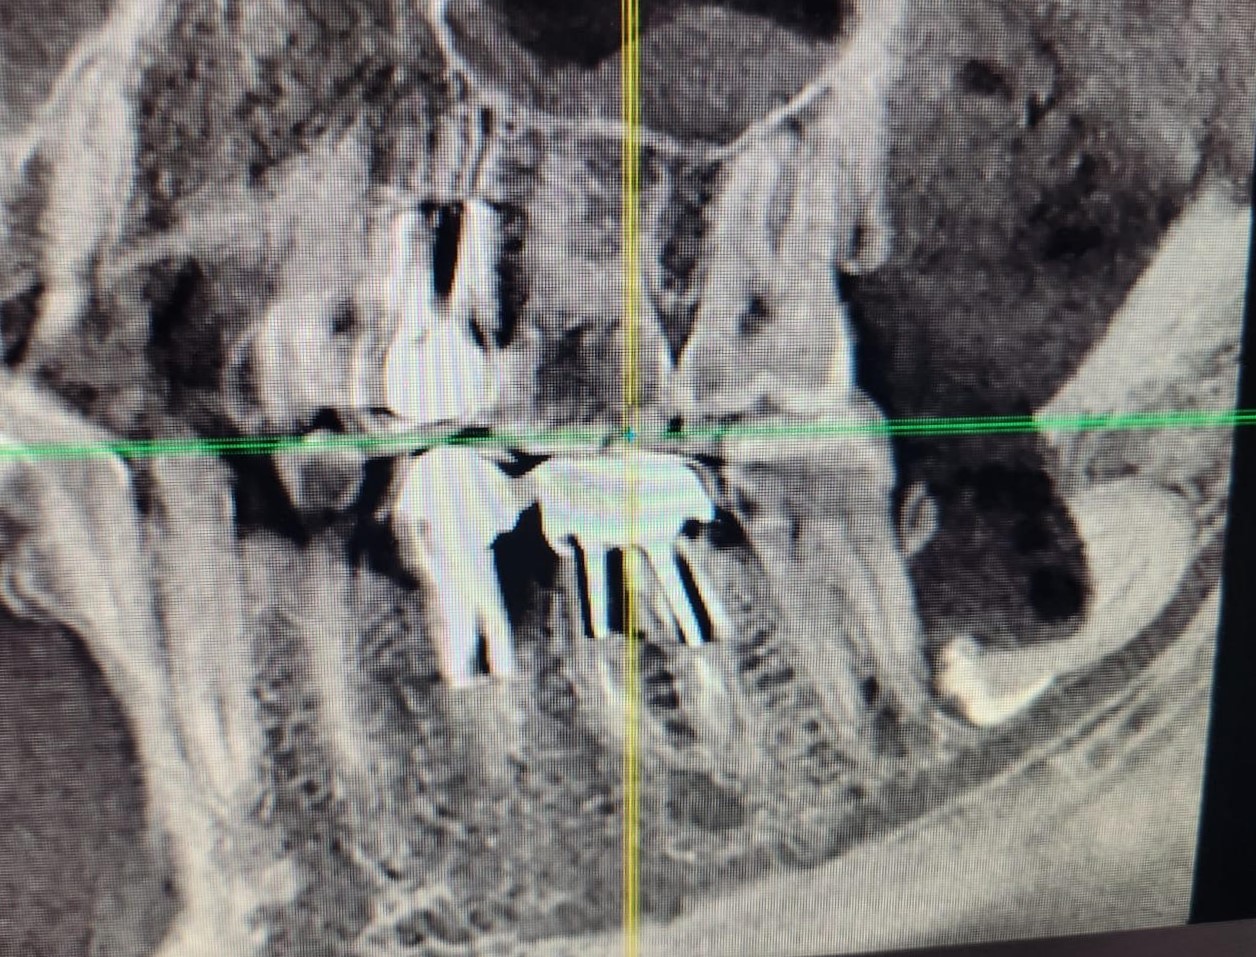

Горизонтальный – зуб мудрости, черная полоска под ним – нижнечелюстной нерв.

Открываю я снимок и вижу, что действительно так и было:

Черная полоска, уходящая в правый нижний угол картинки, отмеченная кружком, и есть то место, где был перебит нерв.

Конечно, меня посещали мысли, что же там такого, что первый раз почти 6 часов пытались удалить зуб, а во второй вообще фиганули нерв. Сделал анестезию, разрез, и удалил зуб за 4 минуты.

Уточняю: 3 минуты ждали, пока подействует анестезия, 4 минуты удаляли зуб, 5 минут накладывали швы, 3 минуты я катал Константина в кресле вверх и вниз. Всё. Меньше 15 минут ушло на удаление остатков зуба мудрости. На целый ушло бы не больше 25.